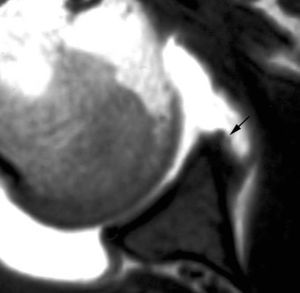

Esta lesión se produce a consecuencia de una tracción repetitiva de la unión cápsulo-perióstica posterior, produciéndose una osificación semejante a un espolón óseo (fig. 15).

Fig. 15.--Lesión de Bennett. Tomografía axial computarizada (TAC) axial (A) y resonancia magnética (RM) T1 axial (B) que revelan la presencia de un «espolón» óseo adyacente al borde glenoideo posterior (flechas en A y B). Nótese la ausencia de una lesión del labio glenoideo posterior en B.